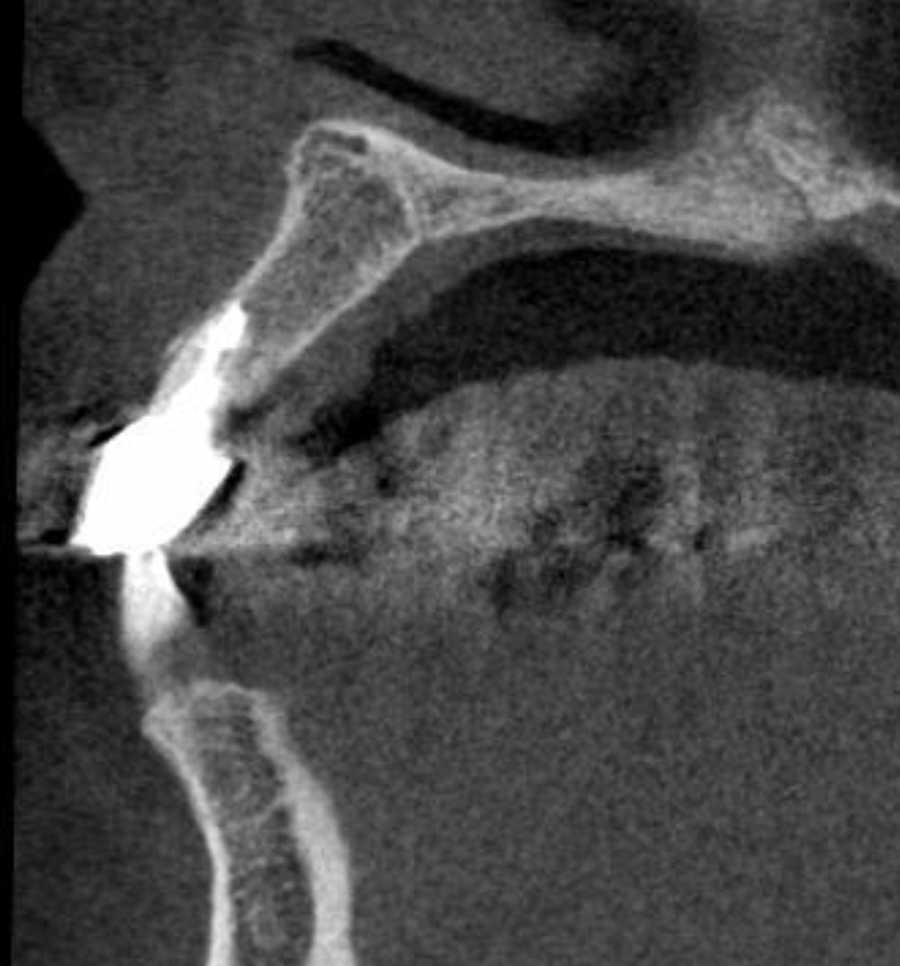

歯周病による前歯部抜歯即時インプラント症例(50代女性)

当日、抜歯とインプラントを同時に入れました。

4本抜歯して2本のインプラントを入れました。

手術直後、1週間後の抜糸時、3か月後の写真です。